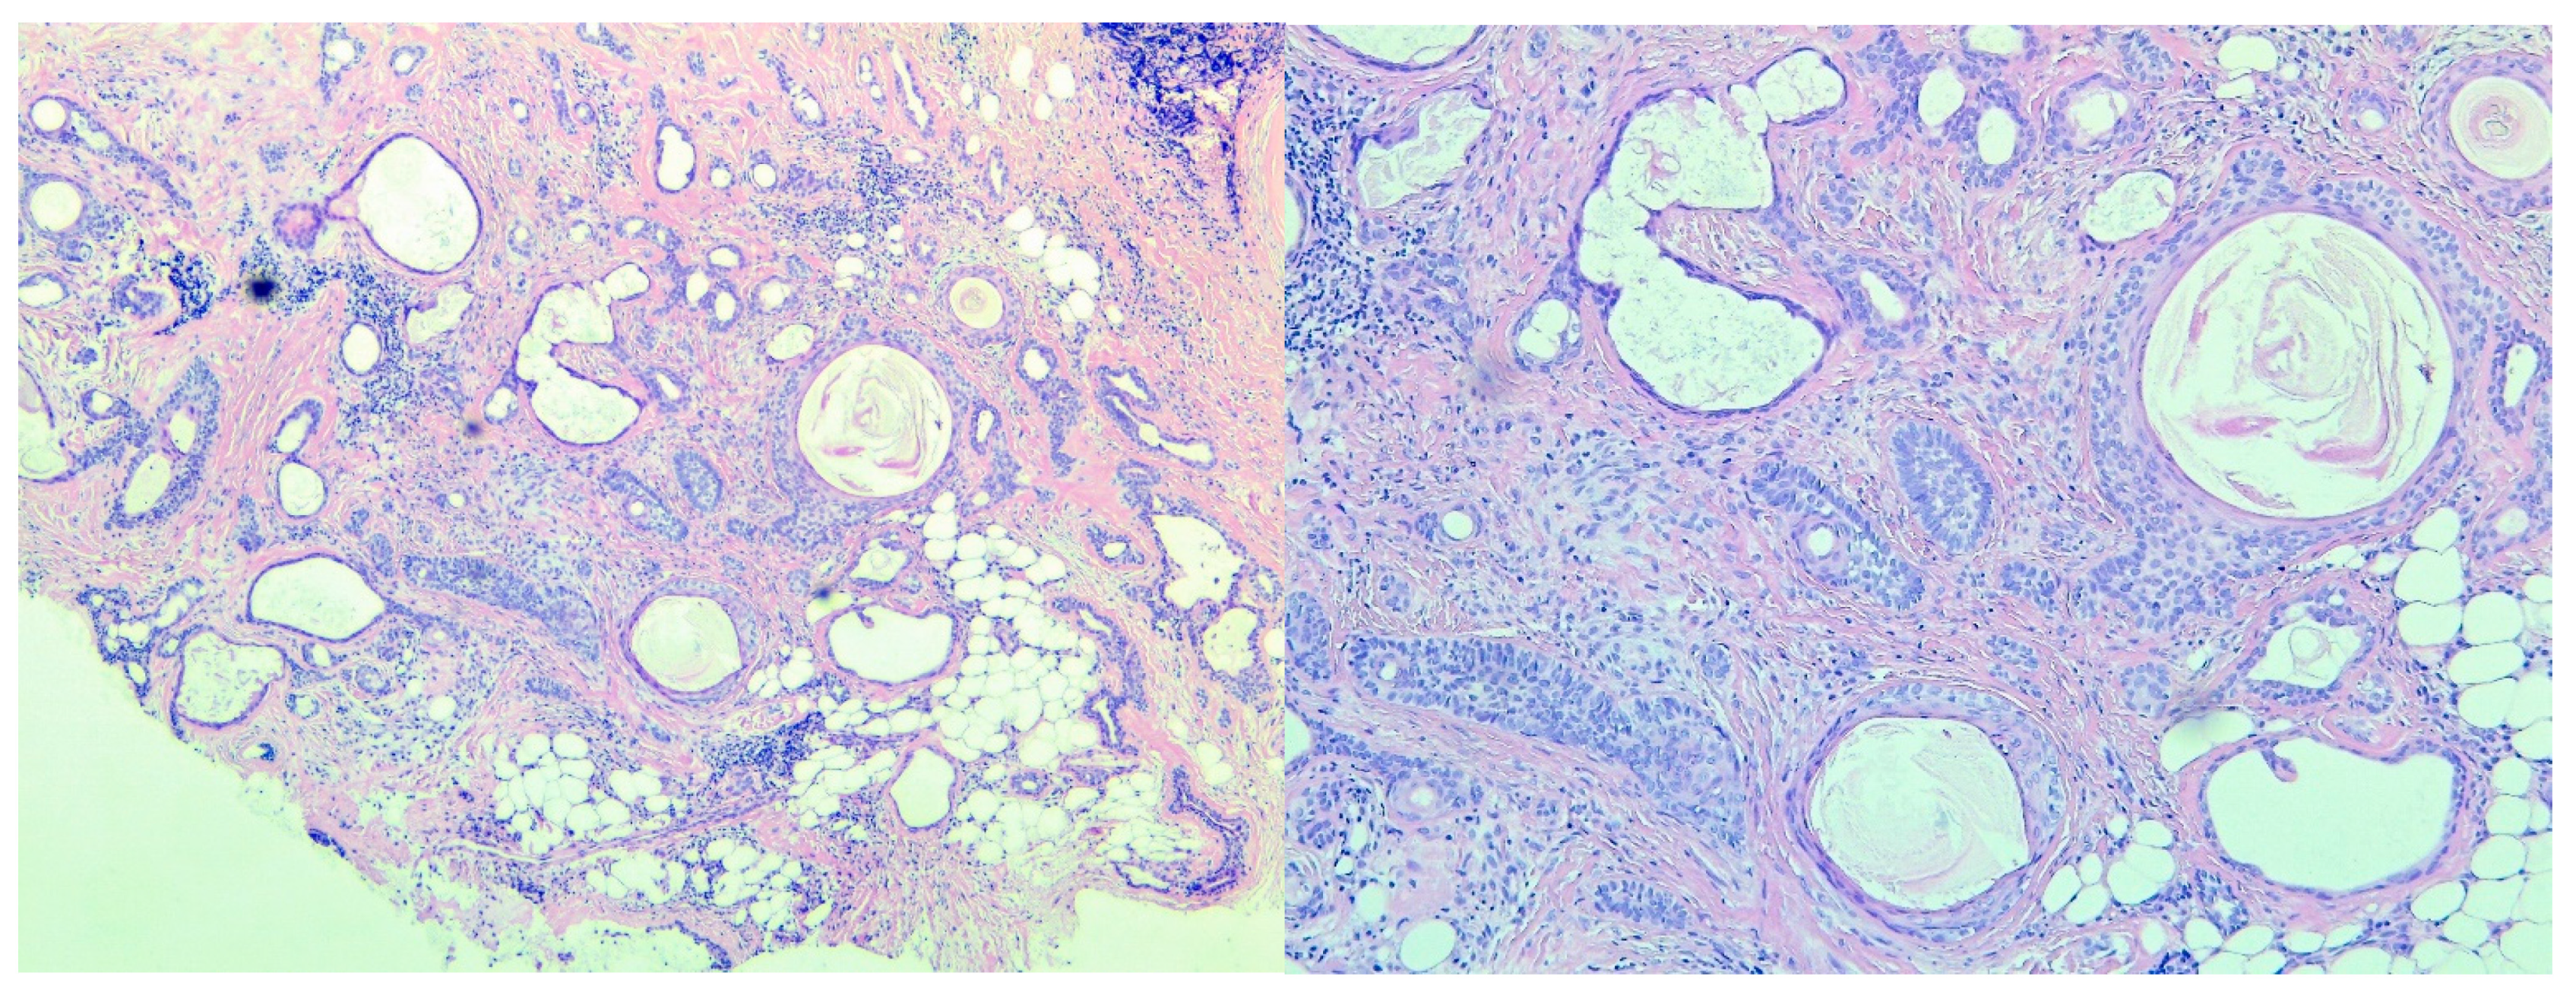

3. Histopathologic Assessment